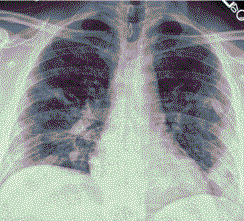

4.3. ЛУЧЕВАЯ ДИАГНОСТИКА COVID-19

Методы лучевой диагностики применяют для выявления COVID-19 пневмоний, их осложнений, дифференциальной диагностики с другими заболеваниями легких, а также для определения степени выраженности и динамики изменений, оценки эффективности проводимой терапии.

Лучевые методы также необходимы для выявления и оценки характера патологических изменений в других анатомических областях и как средства контроля для инвазивных (интервенционных) медицинских вмешательств.

К методам лучевой диагностики патологии ОГК пациентов с предполагаемой/установленной COVID-19 пневмонией относят:

- Обзорную рентгенографию легких (РГ),

- Компьютерную томографию легких (КТ),

- Ультразвуковое исследование легких и плевральных полостей (УЗИ).

Стандартная РГ имеет низкую чувствительность в выявлении начальных изменений в первые дни заболевания и не может применяться для ранней диагностики. Информативность РГ повышается с увеличением длительности течения пневмонии. Рентгенография с использованием передвижных (палатных) аппаратов является основным методом лучевой диагностики патологии ОГК в ОРИТ. Применение передвижного (палатного) аппарата оправдано и для проведения обычных РГ исследований в рентгеновском кабинете. В стационарных условиях относительным преимуществом РГ в сравнении с КТ являются большая пропускная способность. Метод позволяет уверенно выявлять тяжелые формы пневмоний и отек легких различной природы, которые требуют госпитализации, в том числе направления в ОРИТ.

КТ имеет высокую чувствительность в выявлении изменений в легких, характерных для COVID-19. Применение КТ целесообразно для первичной оценки состояния ОГК у пациентов с тяжелыми прогрессирующими формами заболевания, а также для дифференциальной диагностики выявленных изменений и оценки динамики процесса. КТ позволяет выявить характерные изменения в легких у пациентов с COVID-19 еще до появления положительных лабораторных тестов на инфекцию с помощью МАНК. В то же время, КТ выявляет изменения легких у значительного числа пациентов с бессимптомной и легкой формами заболевания, которым не требуется госпитализация. Результаты КТ в этих случаях не влияют на тактику лечения и прогноз заболевания при наличии лабораторного подтверждения COVID-19. Поэтому массовое применение КТ для скрининга асимптомных и легких форм болезни не рекомендуется. При первичном обращении пациента с подозрением на COVID-19 рекомендуется назначать КТ только при наличии клинических и инструментальных признаков дыхательной недостаточности (SpO2 < 95%, ЧДД > 22).